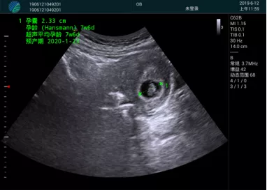

病例一:

清晰顯示孕囊,通過軟件包計算孕齡7w+6d

M20實(shí)時引導(dǎo),術(shù)中清晰顯示孕囊被破壞和抽吸針的過程,清晰顯示吸引針

抽吸結(jié)束后縱切子宮,孕囊已被完全抽吸,未見明顯殘留

橫切子宮,發(fā)現(xiàn)右側(cè)宮腔靠近宮角處有少許脫模樣殘留

M20引導(dǎo)下,抽吸針找到右側(cè)宮角處再次清掃

二次抽吸后再次進(jìn)行超聲檢查,宮腔未見殘留,宮腔線清晰顯示

超聲引導(dǎo)下可視化人流是技術(shù)安全性的保障,一般對人流術(shù)設(shè)備預(yù)算不高,M20具備婦產(chǎn)科軟件包,且穿透力圖像質(zhì)量好,既滿足人流引導(dǎo)需要,也可用于床旁超聲的需求。